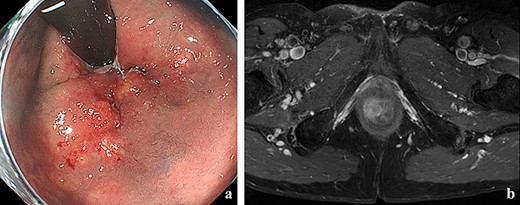

(a) Colonoscopy showed erythema of the mucous membrane from the anal canal to the rectum; (b) MRI showed that the levator ani muscle was ruptured by the tumor.

A 70-year-old man who complained of refractory perianal skin ulcers was referred to our hospital. The condition had spread concentrically around the anus. Colonoscopy revealed erythema of the mucous membrane that was continuous from the anal canal to the rectum (Fig. 1a). Magnetic resonance imaging (MRI) revealed a hyperintense mass in the right wall of the anal canal on T2-weighted images. Tumor invasion of the prostate and levator ani muscle was suspected (Fig. 1b). Enhanced computed tomography (CT) showed a 3-cm wall thickening in the right wall of the anal canal and swelling of the left inguinal lymph node. Fluorine-18 fluorodeoxyglucose positron emission tomography CT (FDG-PET/CT) showed FDG uptake in the anal canal with a maximum standardized uptake value (SUVmax) of 5.4. The left inguinal lymph node had a SUVmax of 2.5. Biopsy was performed on the anal canal and perianal skin lesions. The pathological results indicated adenocarcinoma with severe atypia. Immunohistochemically, the tumor of the perianal skin lesion was positive for cytokeratin 20 (CK20) and caudal homebox transcription factor 2 (CDX2). Based on the above results, the tumor was diagnosed as anal canal adenocarcinoma with PS, inguinal lymph node metastasis and infiltration into the prostate and sphincter. It was decided that radical resection was possible and total pelvic exenteration (TPE) was performed with perianal plastic reconstruction using the gracilis muscle flap and D3 lymphadenectomy (Fig. 2a). The perianal skin lesion was excised with a margin of 1 cm or more (Fig. 2b and c), and simple closure was challenging. The bulbar urethra was pulled out from the perineum to secure a urethral stump (Fig. 2d). The pathological results revealed that the surgical margin was negative. The tumor cells of the anal canal had nuclei with a high nuclear cytoplasmic ratio and infiltrative proliferation with compact nests (Fig. 3a) and were positive for CD56, chromogranin A and synaptophysin. The majority were NEC, and only a few were tubular adenocarcinoma. The Ki-67 labeling index was greater than 70%. The tumor cells of the perianal skin lesions were adenocarcinoma and had no NEC features and were negative for chromogranin A and synaptophysin and positive for CK20 and CDX2 (Fig. 3b–d). In addition, sphincter infiltration and inguinal lymph node metastasis were observed. Accordingly, a diagnosis of anal canal NEC with PS, inguinal lymph node metastasis and sphincter infiltration was made. Although debridement and local flap was required 17 days after the operation because necrosis was observed in a part of the flap, the course after that was generally good. The patient was discharged 42 days postoperatively. At the 7-month follow-up after resection, the patient did not show any recurrence.